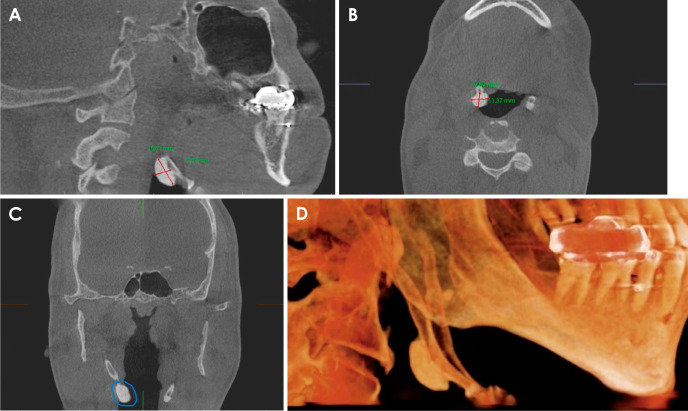

A 54-year-old male patient presented for a periodic check-up at the dental clinic. A panoramic radiograph showed bilateral ossification of the stylohyoid ligament with an oval radiopacity on the right side. Cone-beam computed tomography revealed a well-defined, homogenous hyperdense entity from the lower third of the ossified stylohyoid ligament on the right side. The differential diagnosis of osteoma on the stylohyoid chain includes Eagle syndrome and benign tumors of the stylohyoid chain and adjacent structures. Osteoma rarely manifests in the neck. Even more infrequent are tumors originating from the stylohyoid chain, with only a single documented case of osteoma reported in the literature in 1993. Due to the asymptomatic status, no surgical intervention was advised, and the case would be monitored periodically. This case report describes the details of an osteoma that emerged from the stylohyoid chain, marking it as the second recorded occurrence of this highly rare condition.